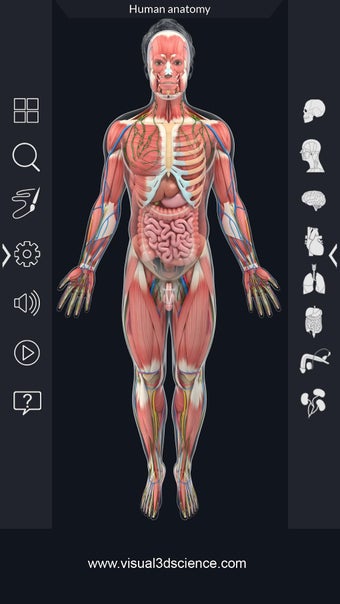

La anatomía humana es una aplicación educativa médica que te permite explorar el cuerpo humano desde todos los ángulos. Ofrece una mirada detallada a la anatomía de los diferentes sistemas, así como a los órganos y sus funciones. Es una referencia perfecta para estudiantes y profesores de medicina.

Puedes seleccionar cada parte del cuerpo por separado para ver su nombre o leer información relacionada. Puedes ocultar y mostrar cada parte del cuerpo, así como rotar 360° alrededor de un modelo 3D altamente realista. Puedes dibujar en la pantalla o compartir capturas de pantalla con tus amigos. Puedes encontrar la definición de cada parte del cuerpo y su anatomía.